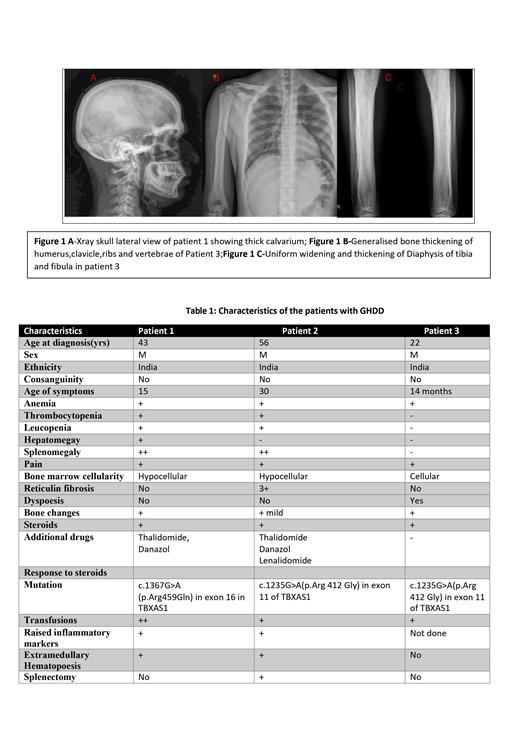

The first patient, a 43-year-old male, had a history of anemia since childhood and became transfusion dependent after 15 years of age. He developed bicytopenia and later pancytopenia with hypocellular bone marrow , along with splenohepatomegaly and extramedullary hematopoiesis in the paravertebral and presacral areas, a novel finding in GHDD cases. Whole exome sequencing revealed a missense mutation in the TBXA2 gene.

The second patient, a 56-year-old male, had a history of anemia since childhood and underwent splenectomy at 46 due to massive splenomegaly and transfusion dependency. However, his transfusion dependency persisted, and bone marrow biopsy suggested myelofibrosis. However he was negativefor myeloid mutations including JAK2. Subsequently, genetic testing revealed a homozygous missense mutation in the TBXAS1 gene. He also developed paraplegia and bladder incontinence, attributed to extramedullary hematopoiesis, which improved with steroid treatment

The third patient a 23 year old man with history of anemia, lower limb tenderness and ecchymosis at 14 months of age. Evaluation then had shown hyperostosis of diaphysis of long bones of lower limbs with sparing of metaphysis and bicytopenia. Was on regular transfusions till 9 years. Re-evaluation with bone marrow studies at 9 years revealed a varying cellular marrow with dysplastic megakaryocytes and diagnosed as pediatric myelodysplatic syndrome ,He was on steroids till 13 years and he did not require further transfusions.He stopped steroids for 1 year following which there was a fall in Hb levels and recurrence of pain in both lower limbs with inability to squat. In view of history of steroid responsive anemia and thickening of diaphysis in X-rays GHDD was suspected and confirmed by genetic testing. He was restarted on steroids and there was a good response to steroids within 4 week with normalisation of hemoglobin levels .